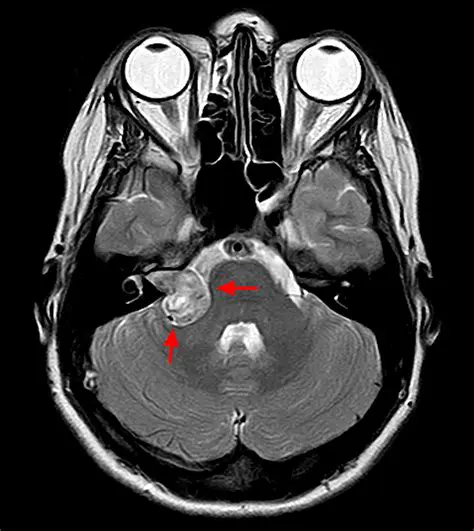

Damage to the auditory nerve